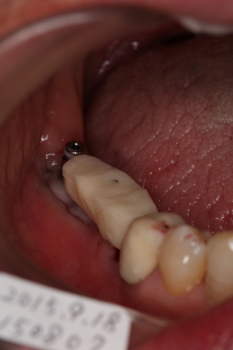

仮歯(テック)を装着。

午前中にインプラントをして、そのインプラント部分で昼ご飯が食べられます。